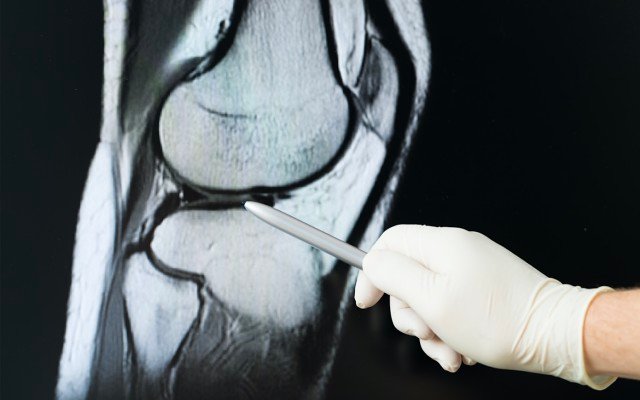

Paradigm Biopharmaceuticals (ASX: PAR) has reported a breakthrough in its phase 2 clinical trial of the injectable pentosan polysulfate (iPPS) treatment drug Zilosul, showing it could act as a cartilage-protective agent and slow cartilage degradation in patients with progressive osteoarthritis of the knee.

The trial has demonstrated a significant reduction in the levels of two key biomarkers – cartilage oligomeric matrix protein (COMP) and ADAMTS-5 – which are associated with cartilage degradation and elevated in the serum of people with advancing osteoarthritis.

The trial data supports iPPS as a cartilage-protective agent which could potentially block the progression of knee osteoarthritis.

Paradigm said the “groundbreaking discovery” suggests that using Zilosul can protect cartilage from progressive degradation as well as reduce pain and improve joint function in osteoarthritic patients.

“It appears to indicate that treatment with Zilosul protects, slows or stops the cartilage around the joint from degrading – slowing the progression of the disease,” it said.